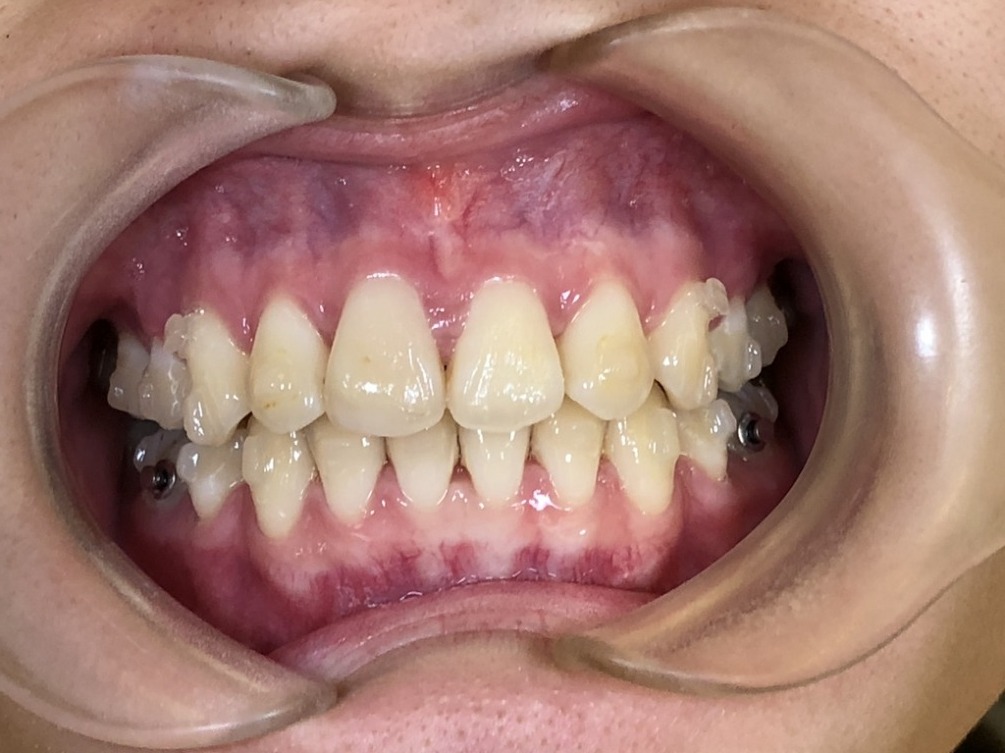

● ① 歯が骨の範囲を超えて動きやすい

骨が薄いと、歯が“外側に動きすぎて”支える骨がなくなり、

歯茎が下がる(歯肉退縮)リスクが高まります。

● ② 根の表面が露出することがある

歯茎が下がると、歯の根が見えてしまい、

知覚過敏・見た目の変化などの問題が出ます。

● ③ 前歯の角度を変える治療で特にリスクが高い

出っ歯を引っ込める、反対に前歯を前に倒す、

こうした“前後の動き”が大きい症例は注意が必要です。